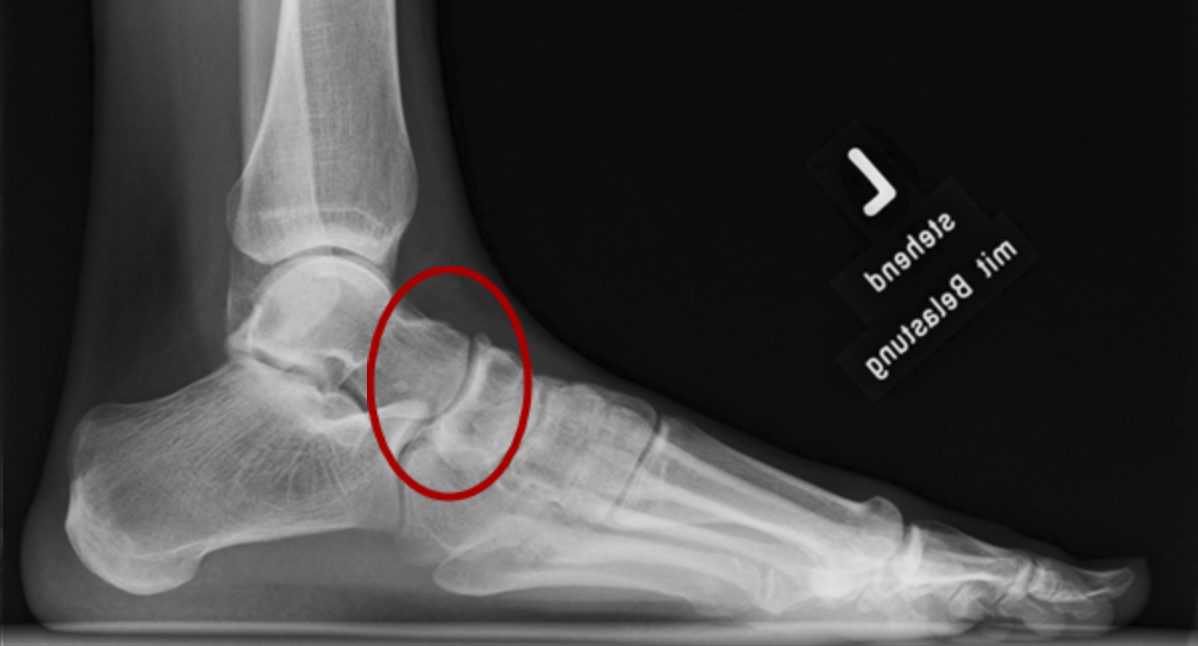

From wupperfuss.de

TalonavicularArthrodese Wuppertaler Fuß Initiative What Is Talonavicular The talonavicular joint is a joint formed by the talus, the bottom half of the ankle joint, and the foot bone immediately in front of it called the navicular. The talonavicular joint is an articulation between the head of talus and the posterior aspect of the navicular bone. The talonavicular joint is an integral part of the chopart joint, alternatively. What Is Talonavicular.